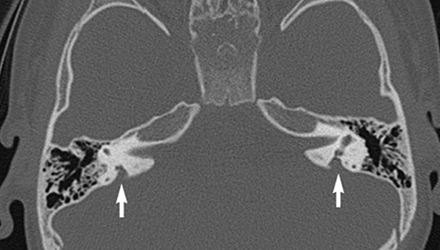

SLC26A4基因定位于人類染色體7q31,SLC26A4基因和大前庭導(dǎo)水管綜合征相關(guān)突變位點的發(fā)現(xiàn),證實SLC26A4是大前庭導(dǎo)水管綜合征的責(zé)任基因。

我們平時提到的“一巴掌打聾”、“一跤摔聾”其實都與SLC26A4基因突變有關(guān),絕大多數(shù)大前庭導(dǎo)水管綜合征都是SLC26A4基因突變?nèi)堑牡湣?/p>

SLC26A4基因編碼一種叫“Pendrin”的跨膜轉(zhuǎn)運蛋白,在機體離子成分平衡的維持中發(fā)揮重要作用。

在內(nèi)耳,Pendrin表達(dá)于內(nèi)淋巴管、內(nèi)淋巴囊、橢圓囊、球囊等處,異變的蛋白將對這些結(jié)構(gòu)的正常生理功能產(chǎn)生影響,引發(fā)聽損。

SLC26A4基因突變導(dǎo)致的大前庭導(dǎo)水管綜合征的典型表現(xiàn)為兒童時期的聽力損失,90%的患者為雙側(cè)性,聽力損失程度不一,可表現(xiàn)為接近正常或重-極重度。

病程可為穩(wěn)定性、進行性或波動性,聽力可逐步下降至全聾;跌倒、撞擊等行為或無外界影響都可能引發(fā)聽力的下降。